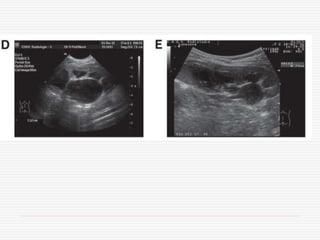

6/12 old boy,febrile UTI by age of 2/12, normal ultrasound and VCUG

9 year-old boy– febrile UTI